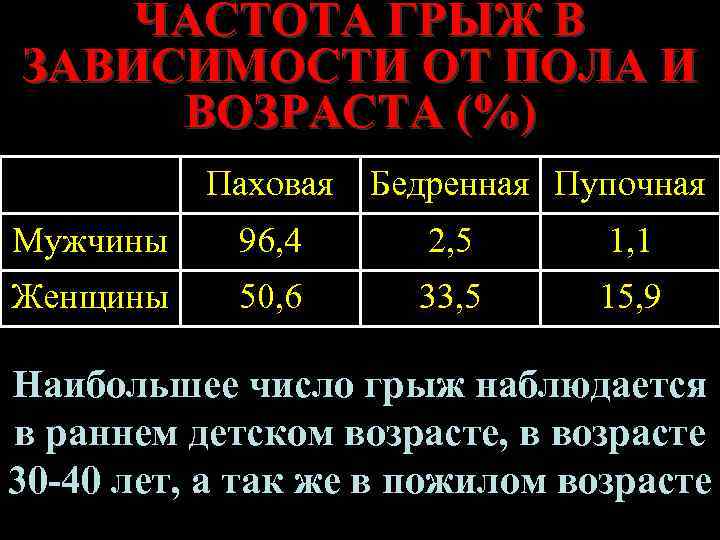

ЧАСТОТА ГРЫЖ В ЗАВИСИМОСТИ ОТ ПОЛА И ВОЗРАСТА (%) Паховая Бедренная Пупочная Мужчины 96, 4 2, 5 1, 1 Женщины 50, 6 33, 5 15, 9 Наибольшее число грыж наблюдается в раннем детском возрасте, в возрасте 30 -40 лет, а так же в пожилом возрасте